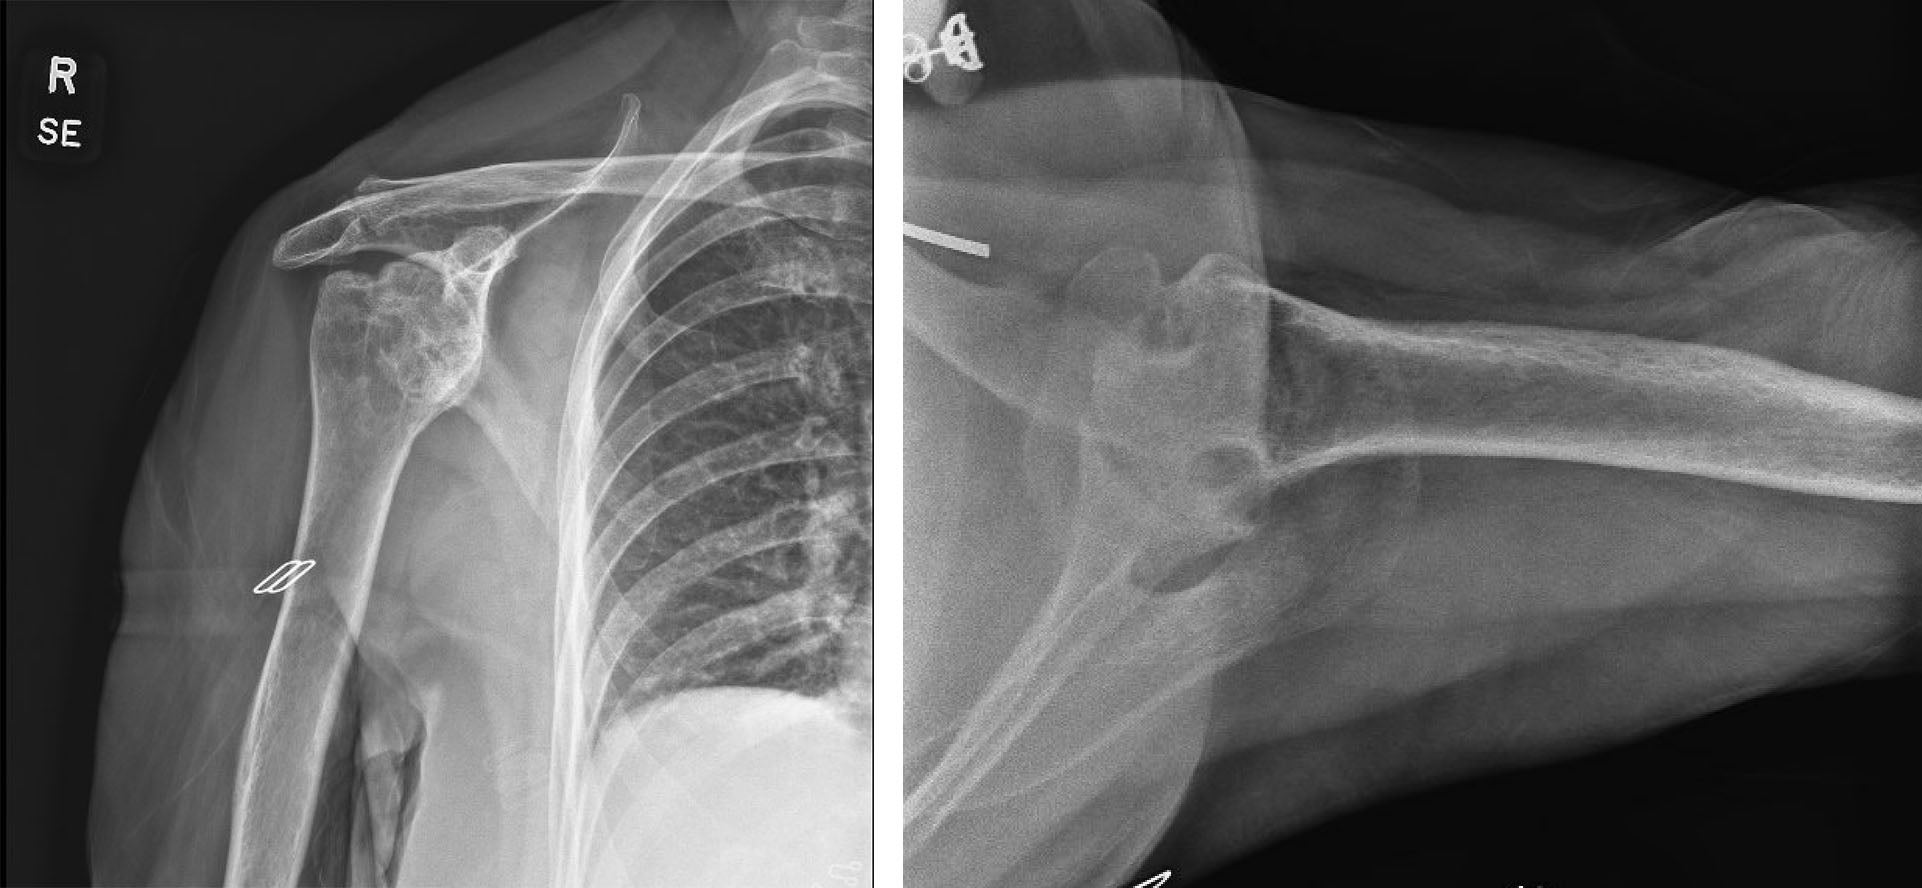

X-rays are also used for the diagnosis of shoulder arthritis. Shoulder x-rays can show bony erosions, narrowing of the shoulder joint space and the development of bone spurs around the shoulder joint. CT scan can also be used to better visualize the amount of bone loss or erosions in the shoulder in cases where shoulder arthritis is severe and chronic.

X-ray showing shoulder arthritis and bone destruction on the socket